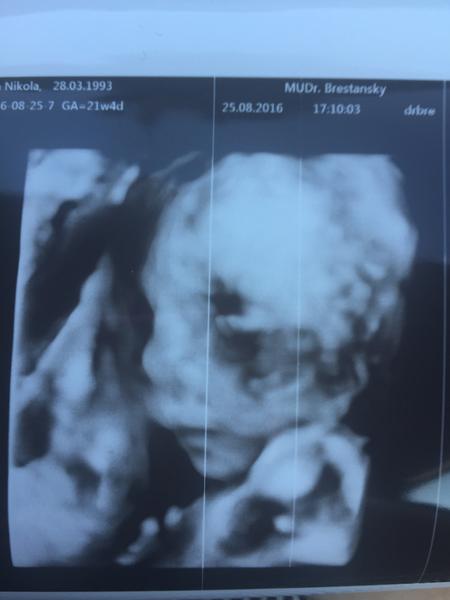

My cakame dievcatko.. viem to uz od 10.tyzdna z baby genu a uz aj na sone sme videli a uz pred tehu som kazdemu hovorila ze ja budem mat dievcatko. A mam 🙂

Nás veľký chlap 416gramovy Nikolasko